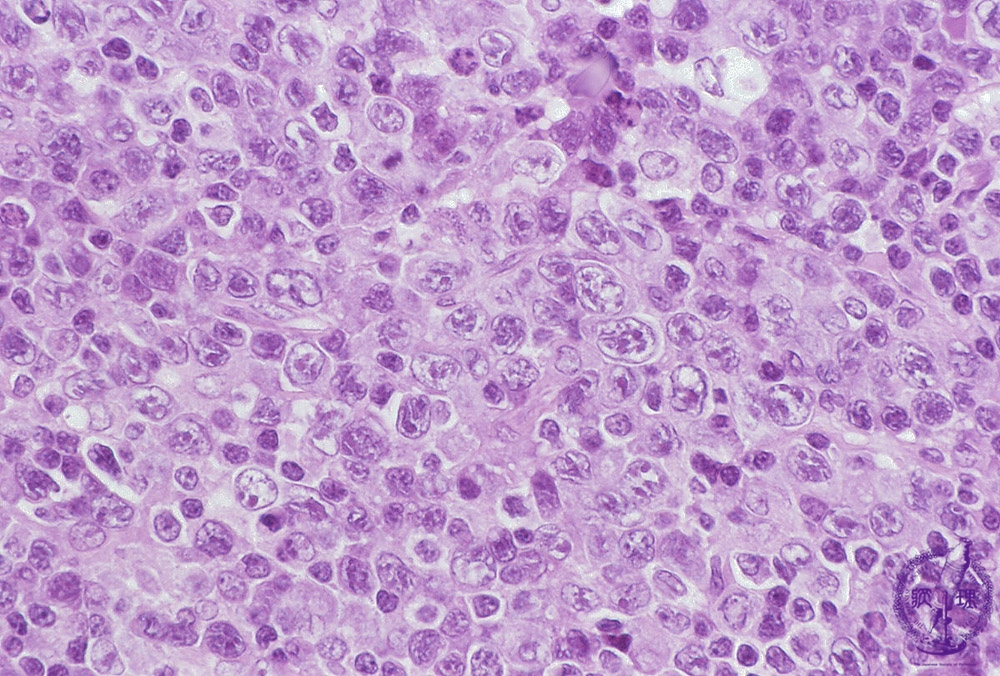

Microscopic image (H&E, high power view): A diffuse proliferation of large, exceedingly atypical tumor cells effaces the underlying lymph node follicular architecture.